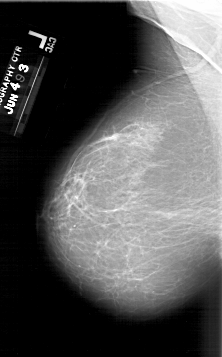

A_1640_1.RIGHT_MLO

A_1640_1.RIGHT_CC

RIGHT_CC LINES 6631 PIXELS_PER_LINE 3901 BITS_PER_PIXEL 12 RESOLUTION 43.5 OVERLAY

RIGHT_MLO LINES 5761 PIXELS_PER_LINE 3166 BITS_PER_PIXEL 12 RESOLUTION 43.5 OVERLAY

FILE: A_1640_1.RIGHT_MLO.OVERLAY

TOTAL_ABNORMALITIES 1

ABNORMALITY 1

LESION_TYPE MASS SHAPE IRREGULAR MARGINS ILL_DEFINED

ASSESSMENT 5

SUBTLETY 3

PATHOLOGY MALIGNANT

FILE: A_1640_1.RIGHT_CC.OVERLAY